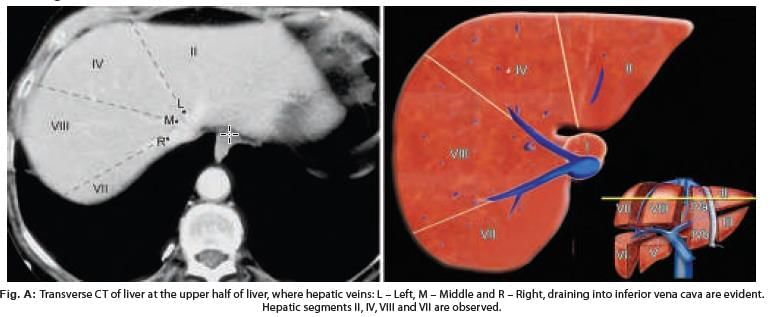

Liver is divided into eight segments according to Couinaud’s classification based upon. (AIIMS May 2019)

In CT scan of liver, identify the arrow marked segment: (INI-CET Nov 2022)